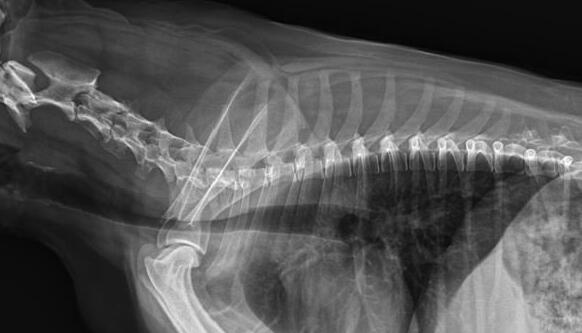

利用宠物dr拍摄图像效果图

1、DR的DQE检测效率可达74%,而传统普通胶片组合X线照片DQE为30%。

2、宠物DR成像速度快,采集时间10ms以下,成像时间仅为3秒,对于受伤的宠物来说,检查越快速,越能早点帮助其治疗,降低痛疼。对于宠物主人而言,也是一种心理安慰。

3、数字图像可进行后处理。图像后处理是数字图像的很大特点。只后要保留原始数据,就可以根据诊断需要,并通过软件功能,有针对性的对图像进行处理,以提高诊断率。

4、兽用dr所具备的辐射剂量较低,相比传统的ct而言,对于宠物和医生而言,都是一种保护。